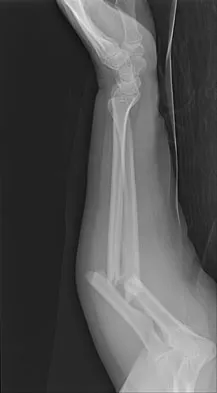

To preserve blood supply to the fractured bone seen in Figures 12a and 12b, care should be taken when exposing which of the following areas?

Explanation